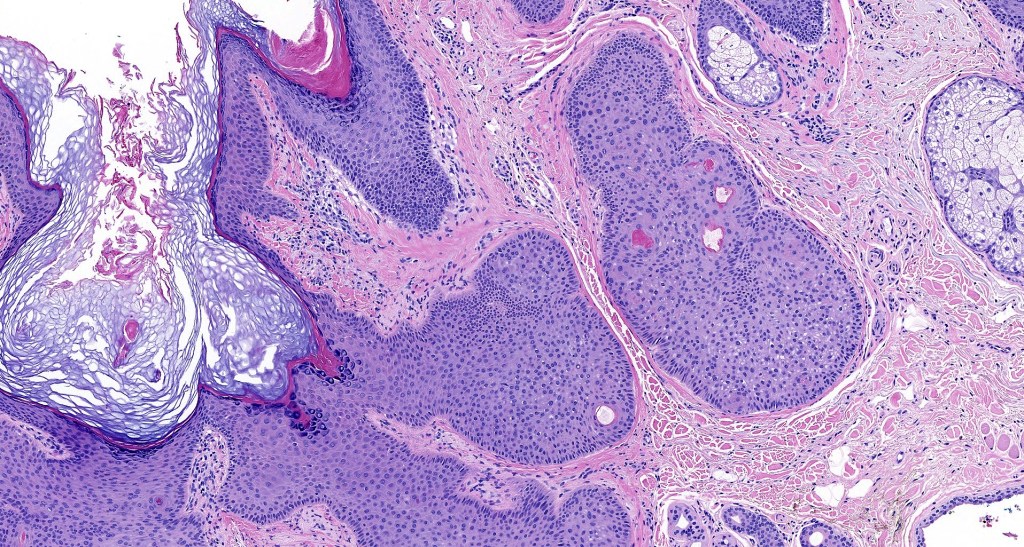

•Multilobulated cyst with associated lobules of well differentiated squamous epithelium

•+/- peripheral palisading

•Eosinophilic basement membrane

•Infundibular>trichilemmal keratinization